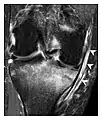

a

b

Figure 7: Fatigue fracture of the talus in a 25-year-old male basketball player with right hind foot and ankle pain, without history of trauma, and a normal initial radiograph (not shown). (a) One-month followup lateral radiograph shows normal appearance. (b) Sagittal T1-weighted MRI shows an irregular fracture line (arrow) within an ill-defined area of hypointensity corresponding to bone marrow edema.[1]